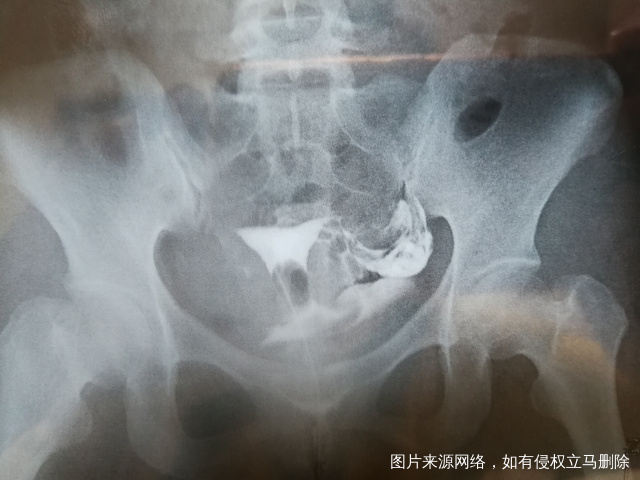

做完输卵管造影第六天了小腹还是感觉沉甸甸的如

可以热敷腹部,如果有发热,腹痛加剧,白带量多,有异味,随时就医